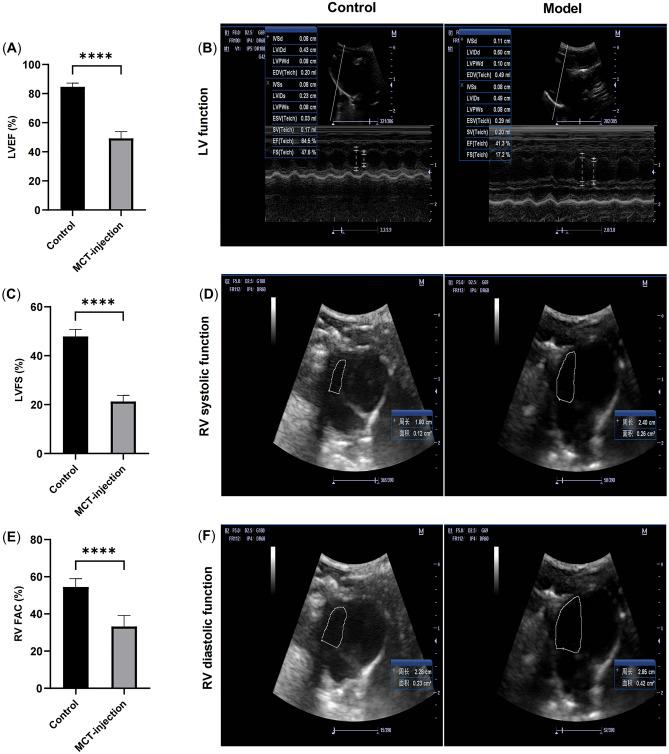

Fat loss predicts adverse outcomes in advanced heart failure (HF). Disrupted circadian clocks are a primary cause of lipid metabolic issues, but it's unclear if this disruption affects fat expenditure in HF. To address this issue, we investigated the effects of disruption of the BMAL1/REV-ERBα circadian rhythmic loop on adipose tissue metabolism in HF.50 Wistar rats were initially divided into control (n = 10) and model (n = 40) groups. The model rats were induced with HF via monocrotaline (MCT) injections, while the control group received equivalent solvent injections. After establishing the HF model, the model group was further subdivided into four groups: normal rhythm (LD), inverted rhythm (DL), lentivirus vector carrying Bmal1 short hairpin RNA (LV-Bmal1 shRNA), and empty lentivirus vector control (LV-Control shRNA) groups, each with 10 rats. The DL subgroup was exposed to a reversed light-dark cycle of 8 h: 16 h (dark: light), while the rest adhered to normal light-dark conditions (light: dark 12 h: 12 h). Histological analyses were conducted using H&E, Oil Red O, and Picrosirius red stains to examine adipose and liver tissues. Immunohistochemical staining, RT-qPCR, and Western blotting were performed to detect markers of lipolysis, lipogenesis, and beiging of white adipose tissue (WAT), while thermogenesis indicators were detected in brown adipose tissue (BAT). The LD group rats exhibited decreased levels of BMAL1 protein, increased levels of REV-ERBα protein, and disrupted circadian circuits in adipose tissue compared to controls. Additionally, HF rats showed reduced adipose mass and increased ectopic lipid deposition, along with smaller adipocytes containing lower lipid content and fibrotic adipose tissue. In the LD group WAT, expression of ATGL, HSL, PKA, and p-PKA proteins increased, alongside elevated mRNA levels of lipase genes (Hsl, Atgl, Peripilin) and FFA β-oxidation genes (Cpt1, acyl-CoA). Conversely, lipogenic gene expression (Scd1, Fas, Mgat, Dgat2) decreased, while beige adipocyte markers (Cd137, Tbx-1, Ucp-1, Zic-1) and UCP-1 protein expression increased. In BAT, HF rats exhibited elevated levels of PKA, p-PKA, and UCP-1 proteins, along with increased expression of thermogenic genes (Ucp-1, Pparγ, Pgc-1α) and lipid transportation genes (Cd36, Fatp-1, Cpt-1). Plasma NT-proBNP levels were higher in LD rats, accompanied by elevated NE and IL-6 levels in adipose tissue. Remarkably, morphologically, the adipocytes in the DL and LV-Bmal1 shRNA groups showed reduced size and lower lipid content, while lipid deposition in the liver was more pronounced in these groups compared to the LD group. At the gene/protein level, the BMAL1/REV-ERBα circadian loop exhibited severe disruption in LV-Bmal1 shRNA rats compared to LD rats. Additionally, there was increased expression of lipase genes, FFA β oxidation genes, and beige adipocyte markers in WAT, as well as higher expression of thermogenic genes and lipid transportation genes in BAT. Furthermore, plasma NT-proBNP levels and adipose tissue levels of NE and IL-6 were elevated in LV-Bmal1 shRNA rats compared with LD rats. The present study demonstrates that disruption of the BMAL1/REV-ERBα circadian rhythmic loop is associated with fat expenditure in HF. This result suggests that restoring circadian rhythms in adipose tissue may help counteract disorders of adipose metabolism and reduce fat loss in HF.